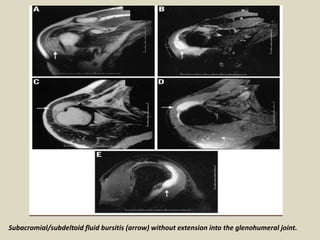

Subacromial/subdeltoid fluid bursitis (arrow) without extension into the glenohumeral joint.

Subacromial/subdeltoid bursitis.